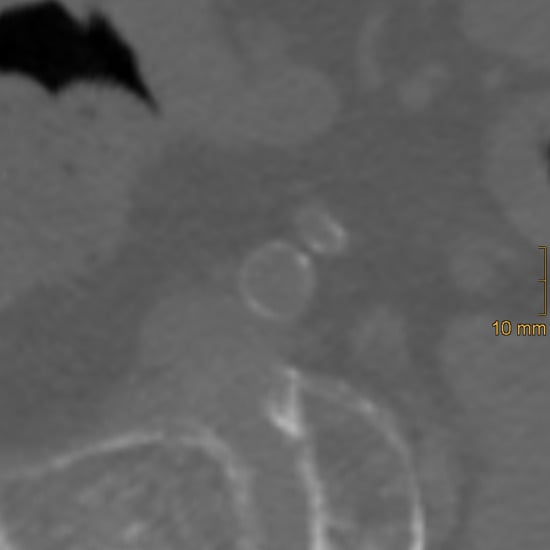

2.2. Assessment of Vascular Calcification

2.2.1. Abdominal Aortic Calcification